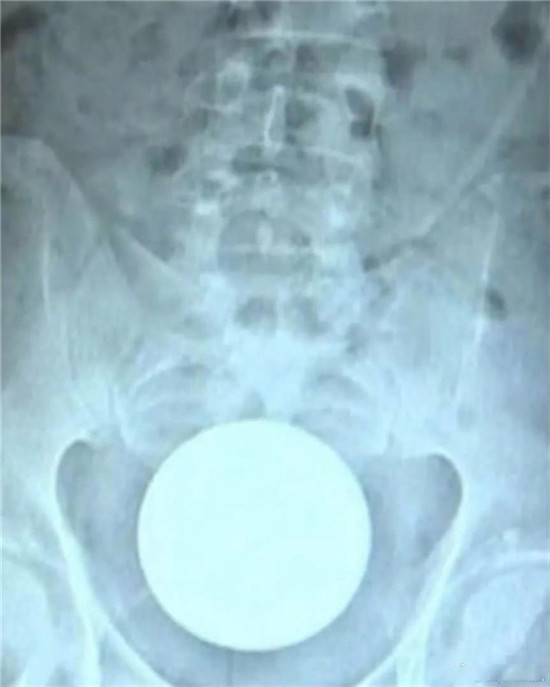

类似的还有圆形的球类的异物。

这是一个直径8厘米的玻璃圆球。

直肠里塞了灯泡或者圆球,是肛门自慰人群的常见意外。

要取出灯泡,需要肛门充分松驰,才能取出来。可以在肛门处打局麻,但是效果不好,不够松,可以打腰麻或者硬麻,当然,最好是全麻,就可以有满意的肛门松驰。

上面图片是产钳,从直肠里把直径8厘米的圆球拽出来。

只要产钳能够夹住灯泡或者圆球,把肛门扩大,可以轻松把灯泡拽出来。不用担心灯泡会碎了。当然,为了保险起见,可以在直肠与肛门处打 润滑油如石蜡油,有润滑后,会更容易拽出来。